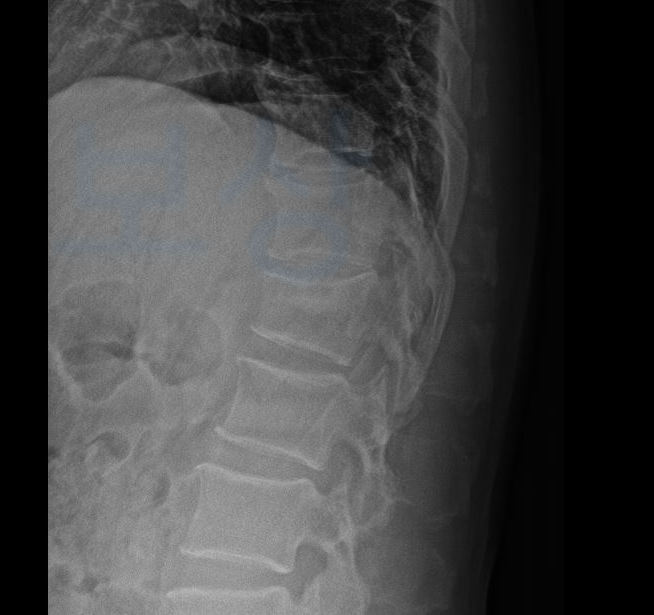

저번에 소개해드렸던 윤@@님 역시 자전거 탑승 중 자동차와의 충돌로 요추골절 진단을 받으셨고 치료가 점점 마무리되어가는 시점, 교통사고 합의금 계산 필요하였습니다. 보상파트너느 의뢰인의 올바른 장해 평가를 위해

공신력있는 제3병원의 전문의로부터

맥브라이드 방식의 후유장해 평가를 의뢰하였고

평가된 장해를 기준으로 의뢰인의 사고경위, 과실, 기존 질병유무 등등 다양한 요인을 고려하여 교통사고 합의금 계산 도와드렸습니다. 추체골절-75%정상-배요부32% 사고관여도100% 7년 한시장해 특인 제도를 활용해 산정한 결과

약 1억 3천만원의

손해배상 금액이 산정되었죠.